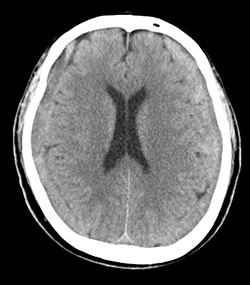

慢性硬膜下血腫 地方独立行政法人大阪府立病院機構 大阪急性期 総合医療センター

慢性硬膜下血腫

慢性硬膜下血腫 対象疾患 医療関係者へ 近畿大学医学部 脳神経外科

慢性硬膜下血腫 対応疾患 流山中央病院 脳神経外科ホームページです 日本脳神経血管内治療学会研修施設 認定病院 脳動脈瘤 クモ膜下 出血 脳出血 脳梗塞などの血管障害だけでなく 脳動静脈奇形や硬膜動静脈瘻といった 珍しい疾患もカバーしています

慢性硬膜下血腫とは 症状 手術法と費用 治療法など 介護のほんね